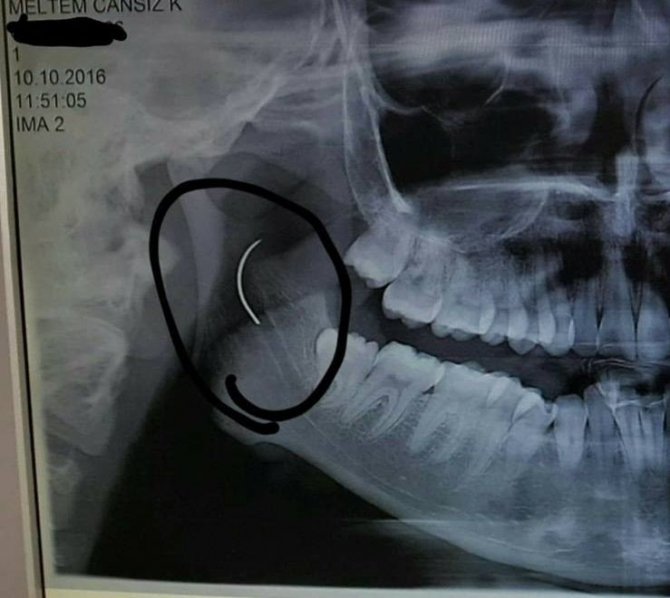

Soma Devlet Hastanesi’nde bademcik şikayetiyle 1999 yılında ameliyat olan Meltem Cansız’ın boğazında iğne unutuldu. 18 yıl boyunca boğazında iğne ile yaşayan ve şu anda 21 yaşında olan Meltem Cansız’ın tüm hayatı acı ve ağrılarla geçti. Boğazındaki iğnenin acıları günden güne yıldan yıla artan Meltem Cansız, 11 yıl sonra 14 yaşında iğnenin fark edilmesiyle Ege Üniversitesi’nde bıçak altına yattı ancak ameliyatı başarısız geçti. Lise öğreniminden sonra sağlık sorunları nedeniyle üniversiteye hazırlanamayan Meltem Cansız, acılarına rağmen yılmadı sabırla bekledi ve geçirdiği başarılı ameliyatla o iğneden 18 yıl sonra kurtuldu.

Boğazındaki iğneyle geçen 18 yılını anlatan Meltem Cansız, "3 yaşında geçirdiğim bademcik ameliyatında iğne boğazımda unutulmuş. Daha sonra iğneden dolayı 11 yıl sonra 14 yaşındayken kulak rahatsızlığım ortaya çıktı. Kafamın sağ tarafı ağrımaya başladı. Doktora gittik, hiçbir şey olmadığını söylediler. Sonrasında beni MR çekilmek üzere Akhisar’a yönlendirdi. Gecenin bir vakti MR’a girdim. Ancak bir türlü çekemediler. Benim üzerimde toka vs. metal bir şey olduğunu söylediler baktılar ancak bir şey yoktu. Üç yada dört defa MR’a girdim. Ancak bir türlü çekemediler. Sonra doktorumuz röntgene yönlendirdi. Röntgen görüntüsünde ameliyattan kalma bir çengelli iğnenin boğazımda olduğu görüldü. Bunun için beni Ege Üniversitesi’ne sevk ettiler. Burada doktorlar bu ameliyatı yapabileceklerini ancak riskinin çok olduğunu söylediler. Biz yine de kabul ettik. 1,5 saatlik operasyon geçirdim ancak iğneyi bulmadıklarını söylediler. 2 sene kadar araştırma yaptık. Birçok hastaneyle görüştük. Ancak ayağımda bir rahatsızlık meydana geldi. Ayağım için Ege Üniversitesi’ne gittik. Tekrardan beni ameliyat eden doktorumla görüştüm. ’Seni ben ameliyat ettim, tekrardan buna kalkışamam’ dedi. MR’a da giremezsin dediler. ’Sen bununla yaşamayı öğren’ en azından bunun için çabalama alınmaması daha iyi dediler. Ben daha genç bir kızım sonuçla bu iğneyle ömür boyu yaşayamazdım. Yaşanan bu olumsuzların ardından araştırmalarımız neticesinde en son İzmir’de özel bir hastaneye gittik. Oradaki doktorum Çağlar Çallı bey bana umut verdi. ’Bu iğneyi alacağız’ dedi. İnancımı kaybetmedim, sonucun ne olacağını bilmeden girdim ben o ameliyata. Ölüm, felç olma riskim çok fazlaydı. ’Yaşayamayabilirsin’ dediler, biz bile bile lades dedik. Sonucu da güzel oldu" dedi.

Ege Üniversitesi’ne gittiklerini belirten baba Cansız, iğnenin şah damarına çok yakın olduğunun söylendiğini belirterek şunları söyledi: "Doktorlar çok tehlikeli bir ameliyat olacağını yanlış ya da en ufak bir hatada kızımızın bir tarafının felç kalabileceğini veya hayatını kaybedebileceğini söylediler. Biz bu riski göze alarak ameliyata müsaade ettik. Fakat iğneyi görüldüğü yerde bulamadıklarını söyleyerek alamadılar. Sonra İzmir Çiğli’de özel bir hastanede denedik. Kendisine binlerce kez teşekkür. Allah razı olsun. Çocuğumun boğazındaki iğneyi aldı. Dünyalar bizim oldu."